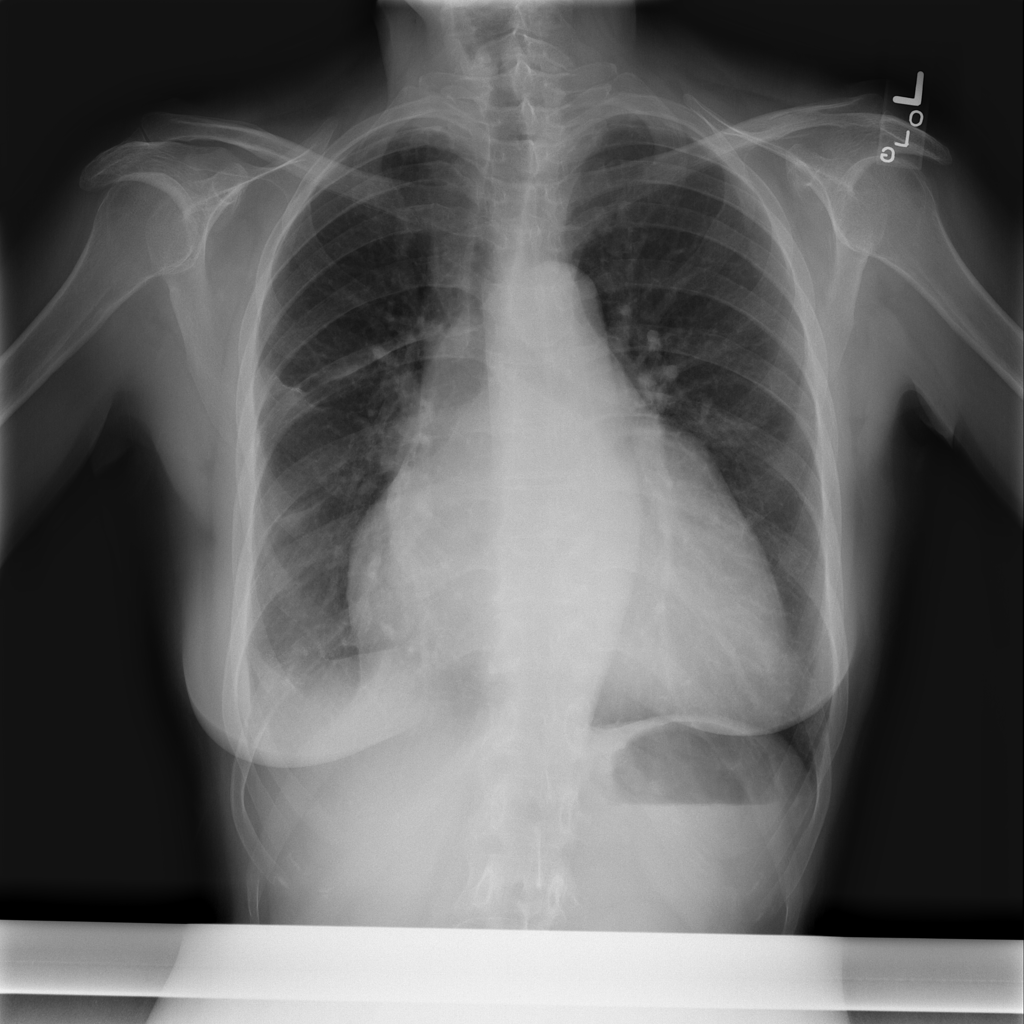

PAT-86C8 · IMG-000Effusion

PAT-86C8 · IMG-000

PA